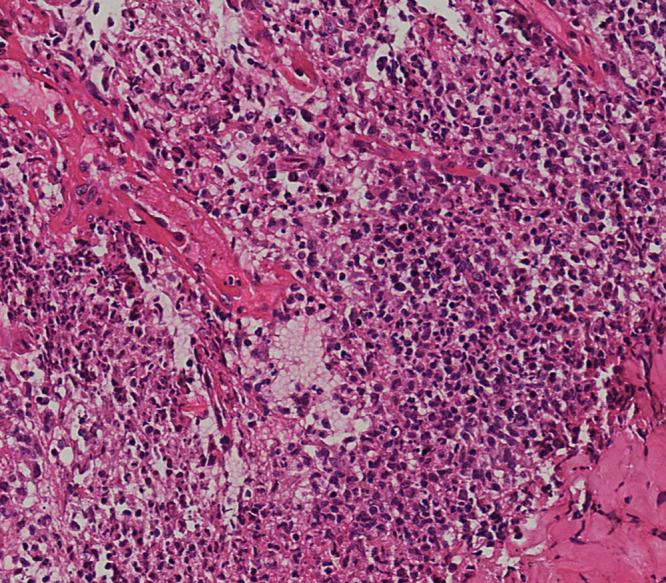

The 11-year-old pediatric patient in the case initially diagnosed with acute febrile neutrophilic dermatosis was eventually confirmed as pustular PG through histopathological examinations of skin and other relevant examinations. The medical condition is lessened after treatment with a combination of glucocorticoids and adalimumab.

该病例中的11岁儿科患者最初被诊断为急性发热性嗜中性皮病,最终通过皮肤组织病理学检查及其他相关检查确诊为脓疱型PG。经糖皮质激素和阿达木单抗联合治疗后病情缓解。